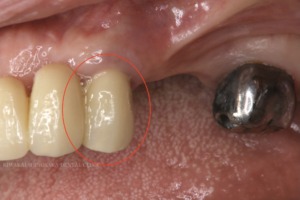

治療前

治療後